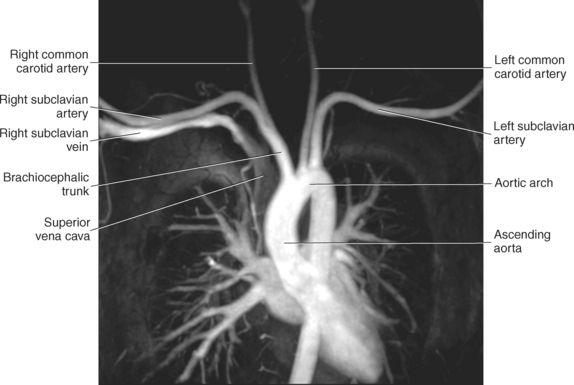

The three main branches of the aortic arch are the brachiocephalic trunk, left common carotid artery, and left subclavian artery (Figure 6.84). The brachiocephalic (innominate) trunk is the first major vessel and the largest branch arising from the aortic arch. It ascends obliquely to the upper border of the right sternoclavicular joint, where it divides into the right common carotid and right subclavian arteries (Figures 6.85 and 6.86). The right common carotid artery ascends the neck lateral to the trachea to the level of C4, where it divides into the right external and internal carotid arteries. The right subclavian artery curves posterior to the clavicle into the axillary region, where it becomes the right axillary artery. The left common carotid artery is the second vessel to branch from the aortic arch. It arises just behind the left sternoclavicular joint and ascends into the neck along the left side of the trachea to the level of C4, where it bifurcates into the left external and internal carotid arteries. The left subclavian artery arises from the aortic arch posterior to the left common carotid artery and arches laterally toward the axilla in a manner similar to that of the right subclavian artery, where it continues as the left axillary artery (Figures 6.85 through 6.88). The right and left internal thoracic arteries arise from the respective subclavian artery at the base of the neck. They run deep to the ribs, just lateral to the sternum, to supply blood to the anterior portion of the thorax (Figure 6.89). The common carotid arteries supply blood to the head and neck, whereas the subclavian arteries supply blood to the upper extremities.

The superior vena cava receives blood from the head and neck via the internal and external jugular veins and from the upper extremities via the subclavian veins (Figures 6.84 and 6.90). The subclavian veins arise from the axillary veins and course posterior to the clavicles. They receive blood from the external jugular veins before uniting with the internal jugular veins behind the sternoclavicular joints, where they continue as the brachiocephalic veins. The left brachiocephalic vein courses across the midline, anterior to the branches of the aorta, to unite with the right brachiocephalic vein just posterior to the costal cartilage of the right first rib. The union of the two brachiocephalic veins forms the superior vena cava, which empties into the right atrium of the heart (Figures 6.75 and 6.76).